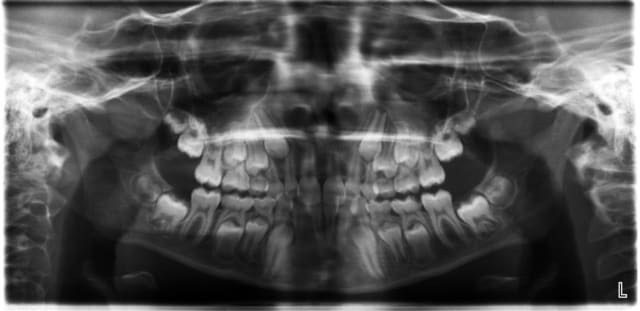

je pense que tu as mal regardé ta télé et que tu t'es fait avoir par la superposition des latérales et des centrales.

> je pense que tu as mal regardé ta télé et que tu t'es fait avoir par la

> superposition des latérales et des centrales.

+1

je crois que la forme très bombée de la couronne de centrale sur la radio, et qu'on ne voit pas sur les photos, est due à la superposition des quartes inciives. Quand au traitement, il s'agit d'un traitement classique d'un cas de classeII div 2.

Attention quand même aux racines des centralesavant de commencer, une retroalvéolaire pourrait être utile.

+1 pour la superposition des racines des centrales et latérales.

regarde bien la téléradio on voit la racine des centrales avec leur apex face vestibulaire de la canine définitive

Il n'y a pas de doute les racines sont normales : car si il y avait un angle si prononcé entre l'axe radiculaire et l'axe coronaire,elles paraîtraient beaucoup plus courtes sur la pano ou la télé de face.